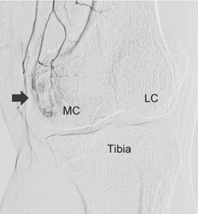

慢性的關節、肌腱、韌帶疼痛,往往伴隨著新生微血管的增生,導致周邊神經敏感度提升而造成長期疼痛;如果能讓這些新生微血管消失,疼痛即可獲得改善。此種治療會在手腕或是鼠蹊部進行局部麻醉,使用極細的導管穿過動脈,找到疼痛部位的新生微血管再注入栓塞的治療藥物,使新生微血管消失、改善疼痛。過程中病人全程清醒,傷口只有針孔大小,術後觀察三十分鐘無不適即可離院;併發症極低,十分安全。治療前的門診評估,會依據每個人不同的疼痛狀況,做詳細的問診、身體及影像學檢查,給患者最好的建議。

膝部退化性關節炎(J Vasc Interv Radiol 2017) 資料來源:中山醫學大學放射科 |

栓塞前